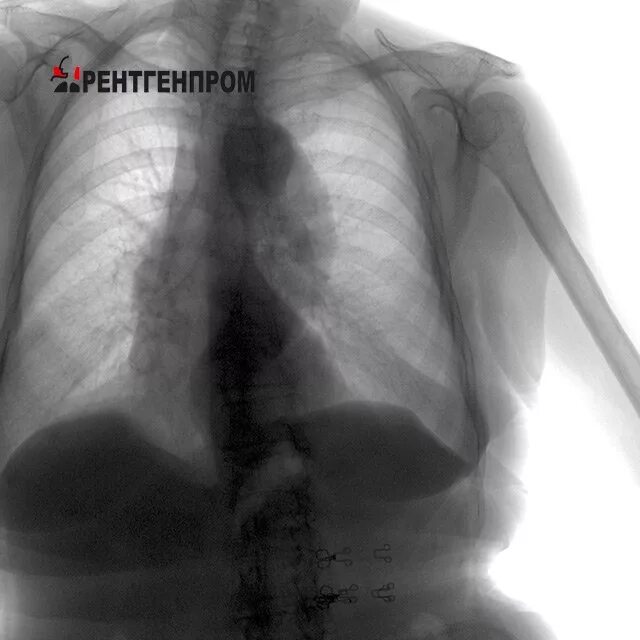

Что значит аорта уплотнена на флюорографии